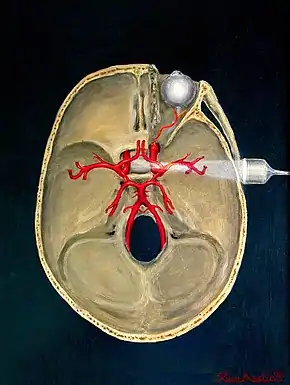

Implantable transcranial Doppler

Sometimes a patient's history and clinical signs suggest a very high risk of stroke. Occlusive stroke causes permanent tissue damage over the following three hours (maybe even 4.5 hours[3]), but not instantly. Various drugs (e.g. aspirin, streptokinase, and tissue plasminogen activator (TPA) in ascending order of effectiveness and cost)[4][5][6] can reverse the stroke process. The problem is how to know immediately that a stroke is happening. One possible way is the use of an implantable transcranial Doppler device "operatively connected to a drug delivery system".[7] Battery-powered, it would use an RF link to a portable computer running a spectral analysis routine together with input from an oximeter (monitoring the degree of blood oxygenation, which a stroke might impair) to make the automatic decision to administer the drug.